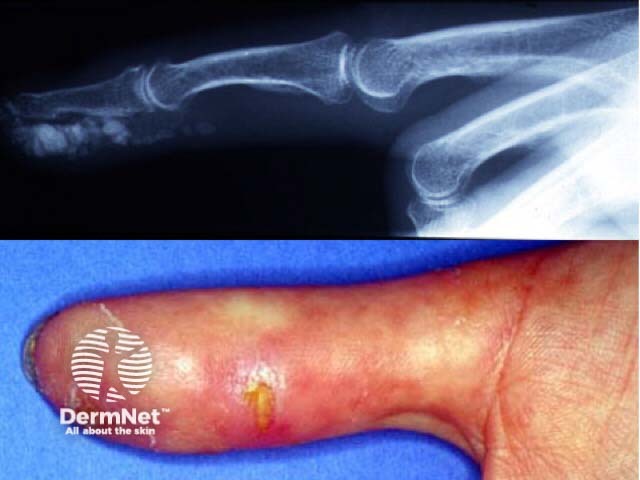

Systemic sclerosis is characterised by progressive accumulation of collagen, fibrosis and loss of mobility of the skin and other organs such as the respiratory and gastrointestinal tracts. it is exceedingly rare in children

The CREST variant (Calcinosis, Raynaud's, oEsophageal, Sclerodactyly, Telangiectasia) may have less severe systemic manifestations.

Severe digital resorption

CRST syndrome

Calcinosis cutis